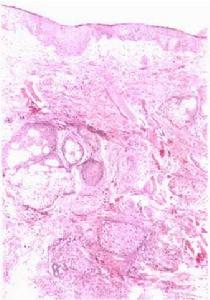

2.據Kesler等報導腫脹的唇部組織病理檢查證實為非特異性棘皮症及上皮下慢性炎症屬肉芽腫性質疑及本病是某些病原體感染所致

唇舌水腫及面癱綜合症2.檢查時除周圍性面神經麻痹及口唇腫脹外常可見舌面腫起或有較深縱向裂溝的舌體。這種舌面裂溝為本綜合徵的特徵性表現。